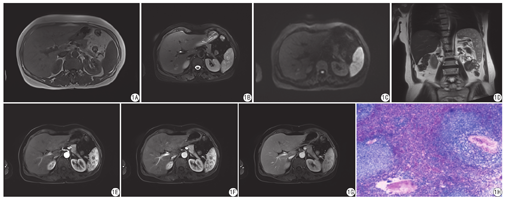

女,60岁,因体检发现脾脏占位入院。查体:腹软,无压痛、反跳痛,脾肋缘下可触及,质韧。实验室检查除血小板计数略低(115×109/L)外,其他血液检测,包括肿瘤标志物、肝肾功能和凝血功能均在正常范围内。外院超声提示脾脏实质回声不均匀,呈结节样改变。本院MR检查:脾脏内可见弥漫性多发小结节影,呈等或稍长T1信号(图1A),T2WI呈(不均匀)高信号(图1B、图1D),扩散加权成像(diffusion-weighted imaging,DWI)高b值(b=800 s/mm2)未见明显扩散受限(图1C);增强后动脉期病变强化不明确,较周围脾实质呈相对低信号,静脉期可见对比剂向内填充,延迟期呈等或低信号(图1E,图1F,图1G);大部分边界清楚,最大直径约13 mm。术前影像诊断:脾脏多发异常信号,脉管源性病变可能性大。行腹腔镜下脾脏切除术,术中见脾脏体积增大,色泽红润,脾周见少量腹水,与周围组织无粘连。游离脾脏,予以切除。术后病理显示送检脾组织内见多个大小不等的窦腔样结构,内衬单层扁平或柱状上皮,部分内皮向腔内突起形成乳头状结构,细胞无明显异型性,腔内充满淡粉红色物,并可见少量红细胞(图1H);免疫组化:CD31(+),F-Ⅷ(+),ERG(+),CD68(+),AAT (+),Lysozyme (+),CD21(-),CD34(-),CD8(-),Ki-67(约2%+)。病理诊断:脾脏窦岸细胞血管瘤(littoral cell angioma,LCA)。

关于脾脏LCA影像表现的报道多为个案或小样本报道[3,4,5]。大体上,LCA的影像学表现可分为多发结节型和单发结节型,前者较多见,本例即为多发结节型。多发结节型LCA病灶大小不等,可呈弥漫性分布,常伴脾脏不同程度肿大。CT平扫多呈等或稍低密度。MR上,T1WI多呈等或稍低信号,边界欠清;T2WI表现为高信号,信号可不均质,部分病变内可因含铁血黄素沉积而呈低信号;增强扫描表现为由周边向中心缓慢填充的渐进性强化模式,但在动脉期因脾脏的花斑样强化LCA病变边缘的强化多被掩盖,因而呈相对低密度/信号。静脉期对比剂可向中心扩展,延迟期表现多样,可呈稍低或等密度/信号[6,7],也可高于周围正常脾实质[4]。本例患者MR表现为脾实质内多发结节样等或稍长T1压脂不均匀长T2信号,动脉期强化不明确呈相对低信号,静脉期部分可见轻度强化,延迟期大部分呈稍低信号,少部分接近等信号,推测可能是因为LCA由不规则血窦吻合构成,血窦窦隙较小强化推进缓慢或延迟扫描时间不足所致。单发结节型,较少见,结节多数较大,脾脏体积不大或仅局部增大,增强动脉期可见明显强化,门脉期强化程度减低趋于均一,延迟期密度/信号与周围正常脾实质相仿,可能因单发结节较大,结节内窦隙囊状扩张,并与周围脾血窦相贯通故而扩散速率加快所致[8]。另外,有文献报道LCA在DWI上呈扩散受限呈高信号[4,7],而本例患者的LCA病灶在DWI上并未出现明显的扩散受限,可能是因为病变由不规则血管腔组成,实性成分相对较少所致。